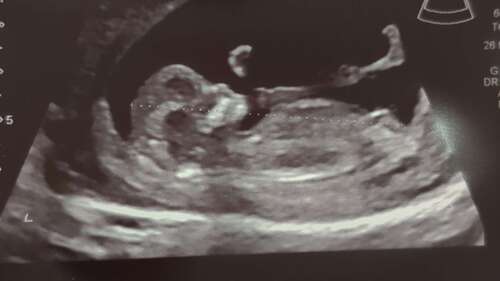

13+5 馃グ wat denken jullie

Ik denk een jongen

Gok een jongen 馃挋 maar heb je meer foto鈥檚?

13 weken en 5 dagen 馃グ Absoluut geen idee of de nub hierop te zien is.. heb ook geen andere foto鈥檚 alleen nog 1 waar alleen het hoofdje op staat.